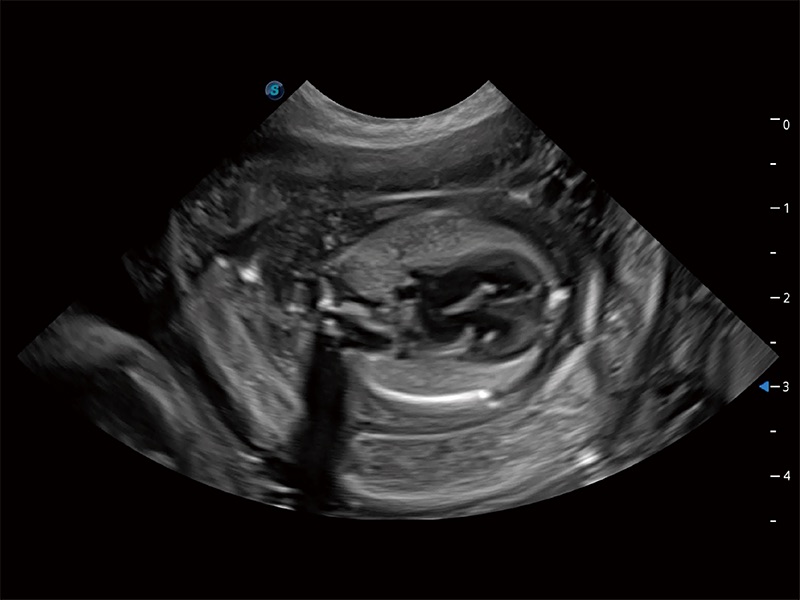

动物是人类最亲密的朋友和最值得信赖的伙伴。1xBET也一直致力于探索动物专用的超声影像解决方案。全新推出的ProPet系列,是1xBET在动物超声影像智能化、专业化、精准化的一次跨越式革新。动物不能用言语来表述自己的不适,通过超声影像,ProPet系列搭建了动物医生与不同物种沟通的“桥梁”,为动物医生注入了“治愈之力”。 ProPet 80 是1xBET匠心打造的一款高端动物专用彩超,采用性能卓越的全新硬件架构,极大提升超声系统的运行效率和数据处理能力,帮助动物医生从容应对日益增多的挑战性病例和日益多样化的临床需求。

高性能和先进的临床应用工具可以为动物医生提供临床信心。ProPet 80 搭载了先进的腹部和浅表应用工具,帮助医生在日常临床实践中发挥前所未有的作用。

ProPet 80 全新的动物超声智能软件和丰富的探头群,为动物医生提供了高清晰度和精细分辨率的图像,无论在宠物、马科、畜牧还是实验室动物等应用中都可以轻松应对,为您的日常工作带来满意的体验。